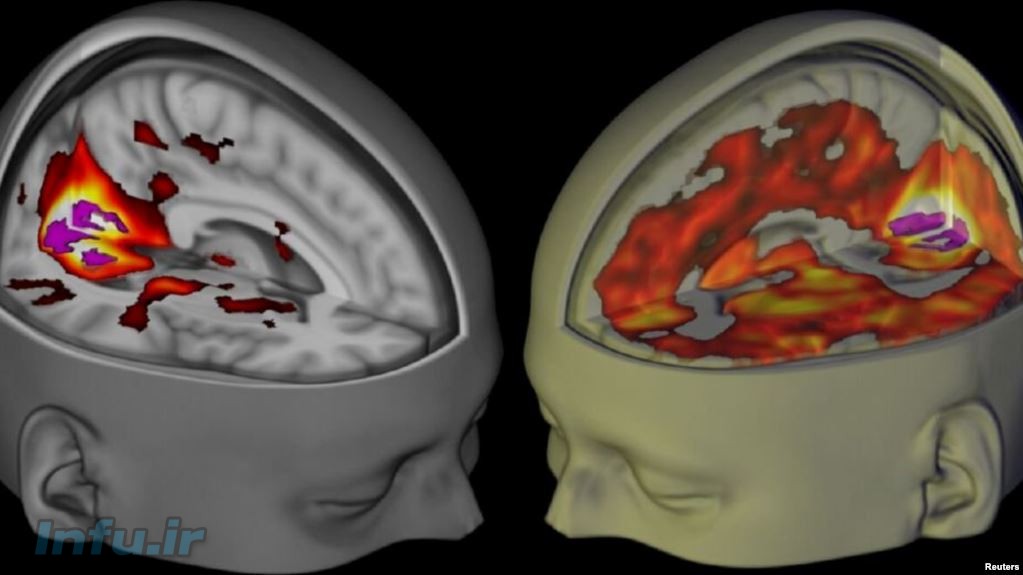

یک نقشه تازه از مغز، نزدیک به صد منطقه تازه در این عضو حیاتی بدن را برای نخستین بار نشان میدهد.

به تازگی محققان نقشه تازهای از مغز انسان را منتشر کردند که به عقیده متخصصان نقطه عطفی در دانش عصب شناسی بهشمار میآید. این نقشه نزدیک به صد منطقه تازه در مغز را که قبلا شناسایی نشده بود، نشان میدهد.

به گزارش هافتینگتون پست این نقشه توسط اسکنرهای پیشرفته و کامپیوترهای مخصوص هوش مصنوعی طراحی شده است.

اطلاعات لازم برای طراحی این نقشه از صدها مغز مورد مطالعه دریافت شده است. این نقشه از تمام نقشههای مغز موجود بسیار پیشرفتهتر است.